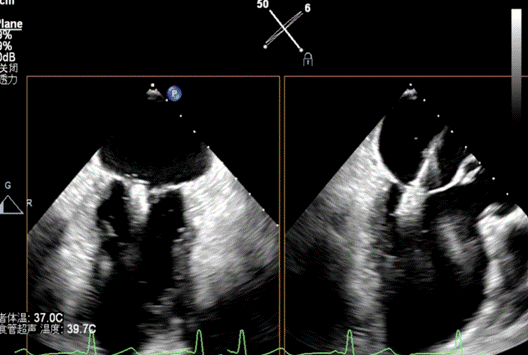

患者全麻成功后,经右股静脉建立路径,穿刺房间隔,瓣膜夹通过输送系统送入左心房,顺利到达病变二尖瓣区域。在经食道超声和DSA的辅助下,通过反复评估二尖瓣返流位置、抓捕位置、返流程度,最终在A2P2位置植入一枚DragonFly™夹子。手术操作时长48分钟,透视时间总计为5分钟,术后患者无不适感,整个手术流畅完美,患者返流程度降至微量。

检查,诊断为慢性心脏功能不全急性加重,缺血性心肌病,二尖瓣关闭不全(重度),心功能Ⅱ级,术前经胸超声检查提示二尖瓣关闭不全(A1、A2区及P2区)重度,二尖瓣返流束宽度3.0cm,有效返流口面积(EROA)=0.52cm²,二尖瓣返流面积14.3cm²,左室射血分数(LVEF)为36%。

患者全麻成功后,经右股静脉建立路径,穿刺房间隔,瓣膜夹通过输送系统送入左心房,顺利到达病变二尖瓣区域。在经食道超声和DSA的辅助下,通过反复评估二尖瓣返流位置、抓捕位置、返流程度,最终决定在A2P2位置植入俩枚DragonFly™夹子,显著改善了患者的返流情况。手术操作时长60分钟,透视时间总计为15分钟。术后患者无不适感,整个手术流畅完美,患者返流程度从重度降至轻度。